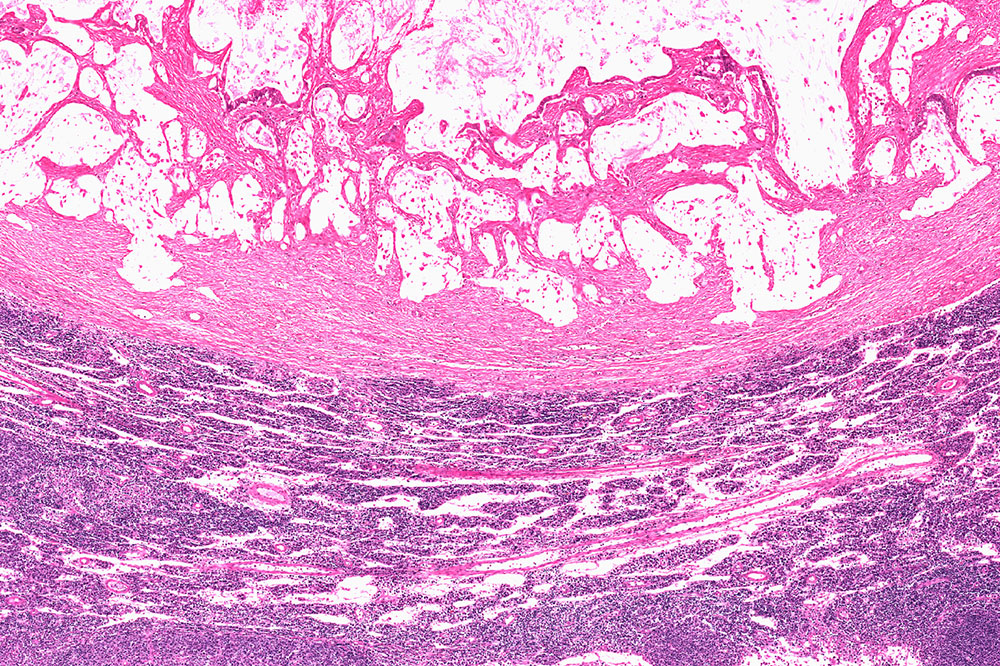

Gastrointestinal stromal tumors (GIST) are a rare form of cancer that occurs in the digestive tract, with the majority found in the stomach. GIST is a type of sarcoma, originating from the interstitial cells of Cajal, which help regulate digestive movements. While relatively uncommon, GIST can be a serious condition that requires specialized treatment.

GIST is a type of tumor that forms in the gastrointestinal tract, most commonly in the stomach or small intestine. These tumors are generally caused by mutations in certain genes that control the development of gastrointestinal cells, particularly the KIT gene or PDGFRA gene. Unlike more common types of stomach cancer, GISTs are rare and often grow slowly. However, they can metastasize if not treated promptly.